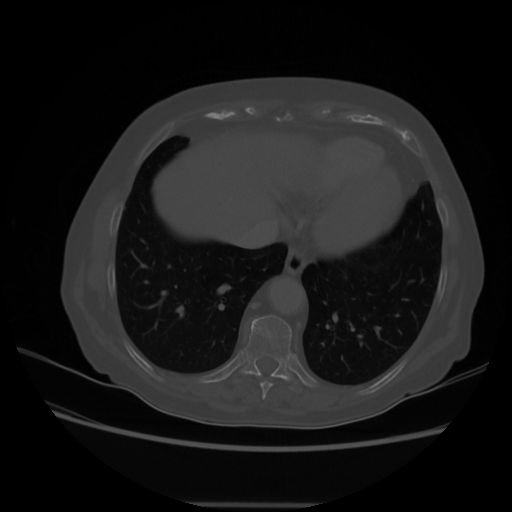

Reconstructed NATIVE CT scan (cycle consistency)

Full window (WL 1023.5, WW 4095 β†’ Low βˆ’1024, High +3071)

Lung window (WL -600, WW 1500 β†’ Low βˆ’1350, High +150)